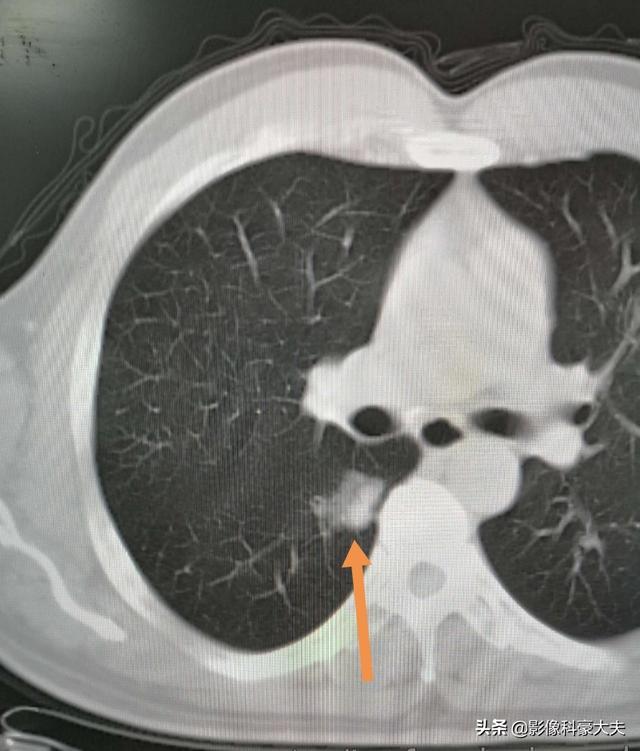

明らかに悪性の徴候のある結節、例えば、小葉状でバリがあり、血液を供給する血管がある結節は、積極的な介入、通常は生検または手術が推奨される。

良性結節や悪性の可能性のある結節など、悪性の徴候を示さない結節に対しては、通常、経過観察が推奨される。良性結節は経過観察中に再吸収したり、変化がなかったりするが、悪性の可能性のある結節は徐々に姿を現すことがあり、悪性結節と同様に治療される。